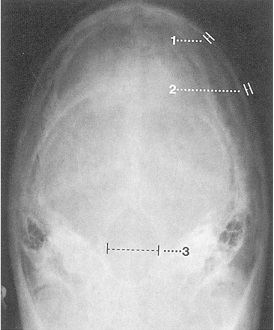

Рентгенограмма затылочной кости

Отображаемая часть свода черепа имеет нормальную форму, толщину и характеризуется симметрией деталей.

Равномерные костная структура и минеральное содержание (плотность). Контуры свода черепа ровные и четкие, без патологических перерывов или линий перелома. Нормальная форма, ширина и контуры большого отверстия затылочной кости. Полость черепа выглядит обычно. Мягкие ткани равномерной толщины.

Нормальное отображение затылочной кости и большого отверстия.

Ширина внутренней пластинки: примерно 1,5 мм

Ширина наружной пластинки: примерно 0,5 мм

Ширина большого отверстия затылочной кости: примерно 3,5 мм

(осторожно: проекционные искажения)